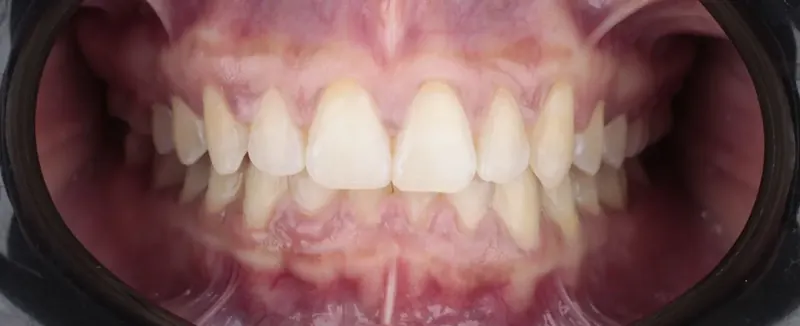

Brackets y diseño de sonrisa con flujo digital. Función y estética con mínima invasión.

• “Ortodoncia, prótesis y diseño de sonrisa con tecnología digital 3D.”